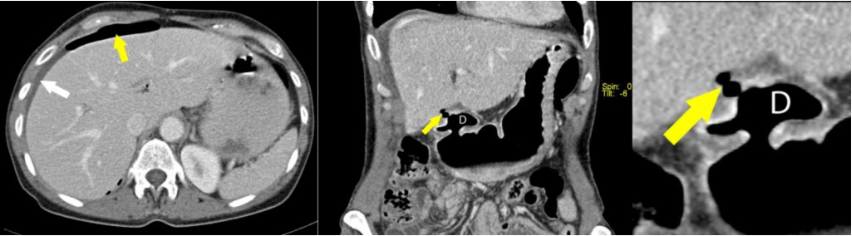

Hydronefrose:

18

Q

Diagnose?